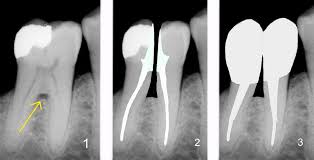

La premolarización es un tratamiento poco frecuente aunque, a veces efectivo, en pacientes periodontales (con enfermedad de las encías) donde los molares inferiores se ven afectados en la furca.

La furca de un molar es la zona donde se dividen las dos raíces que poseen (marcado con la flecha amarilla en la imagen 1)

Una vez realizada la endodoncia (tratamientos de conductos) [Imagen 2], si la pieza dental tiene buen pronóstico y suficiente cantidad ósea, se puede dividir en dos mitades, para después reconstruirlas mediante empastes o fundas de cerámica para convertir ese molar afectado en dos premolares, o en uno solo si, el diagnóstico y plan de tratamiento requiere la extracción de una de las dos mitades.